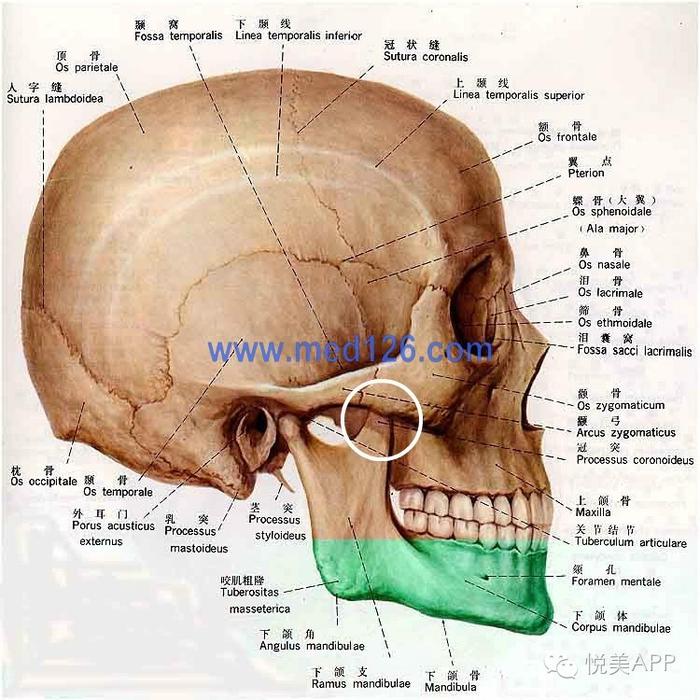

下颌骨喙突位置:

也就是白色圆圈内的两块骨头距离,推太多会导致张口受限,影响功能

咬肌上端附着于颧骨颧弓的下方和后方,下端附着于下颌角,下颌升支。承担主要的咀嚼功能。

长期的进食咀嚼,咬肌的收缩对颧弓颧骨下方施加持续的张力,是造成颧弓颧骨手术后颧弓骨块下移的主要因素。